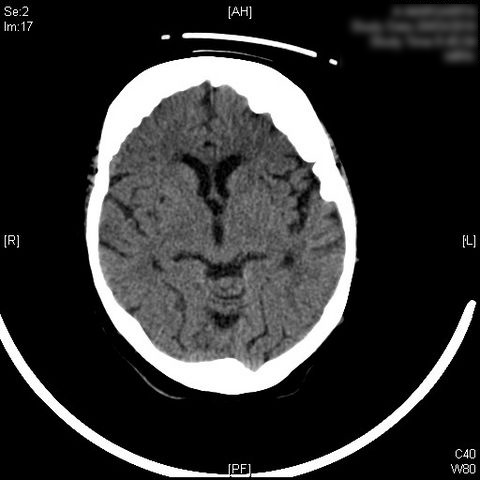

AVC amplio de territorio de A. cerebral media

Atrofia cortico-subcortical de predominio frontotemporal.